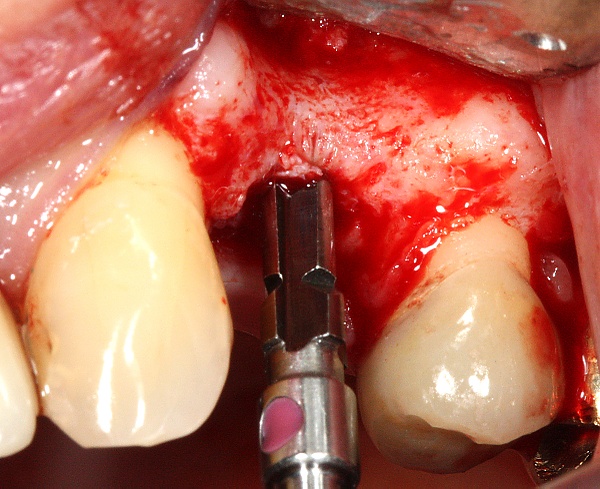

Техника

При планировании зубных имплантатов основное внимание уделяется общему состоянию здоровья пациента, местному состоянию здоровья слизистых оболочек и челюстей, а также форме, размеру и положению костей челюстей, соседних и противолежащих зубов.

Особое значение имеет уровень гигиены полости рта. Имплантация не может быть выполнена без санации полости рта (все зубы должны быть вылечены), поскольку любой очаг инфекции в организме может свести на нет работу имплантолога из-за высокой вероятности последующего отторжения вживлённого имплантата.

Установка зубных имплантатов может вести к периимплантиту, который возникает из-за бактериальной флоры, попадающей на внешнюю поверхность имплантатов через зубной налет. Лечение данного заболевания проводили корейские исследователи с использованием титановой щетки.